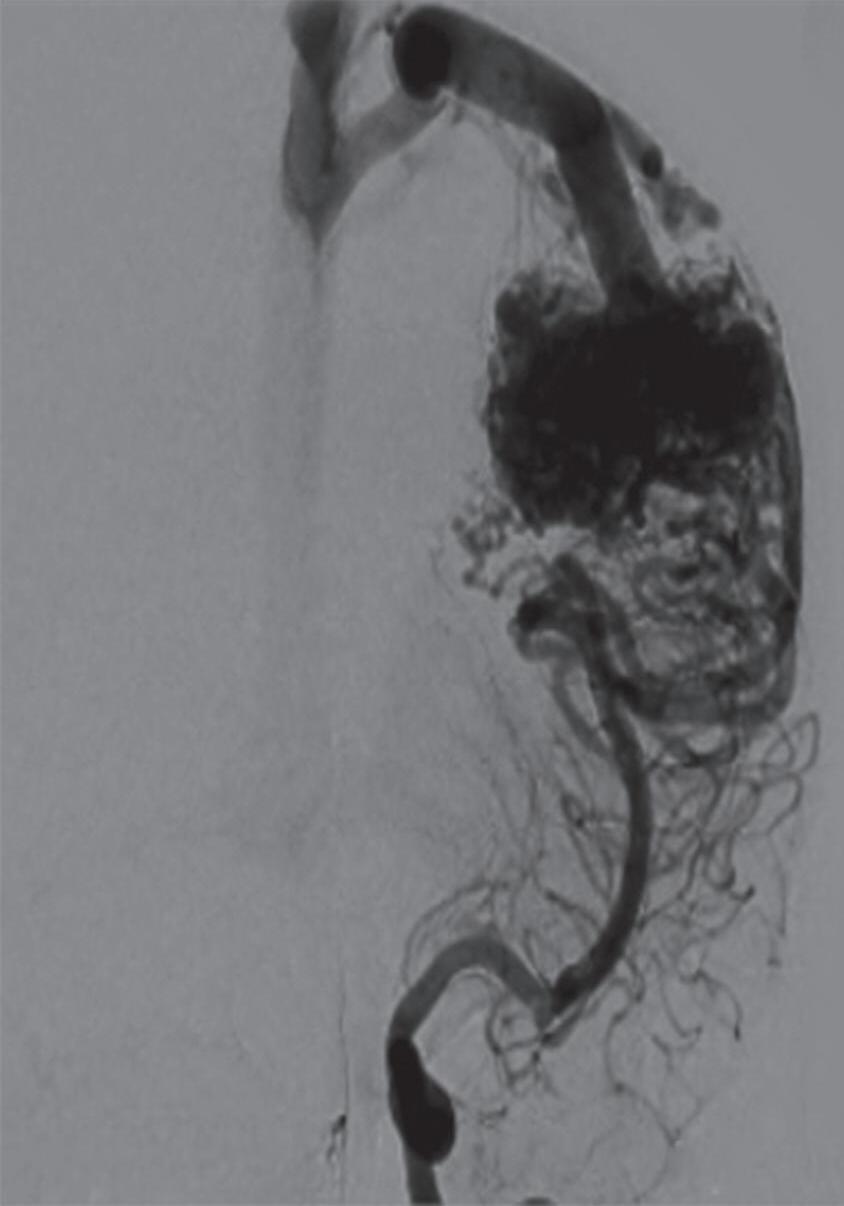

Com relação ao fluxo no interior do nidus, alguns autores classificam-nas em alto fluxo (Fig. 1-8) e baixo fluxo (Fig. 1-9). São consideradas de alto fluxo aquelas em que a opacificação após injeção de contraste ocorre apenas na malformação, em contrapartida, nas de baixo fluxo, ocorre opacificação da MAV e de outras artérias normais do mesmo território vascular. Exemplificando as lesões de alto fluxo temos as malformações arteriais, as malformações arteriovenosas e as fístulas arteriovenosas, enquanto as lesões de baixo fluxo são representadas pelas malformações venosas, linfáticas e capilares.25

Fig. 1-8. (a-c) RNM T1 com contraste, cortes sagital (a), coronal (b) e axial (c) demonstrando MAV não rota com nidus localizado no lobo occipital à esquerda (setas longas). (d) Arteriografia digital cerebral com injeção de contraste via carótida direita (AP) mostrando a contribuição da carótida direita na irrigação da MAV contralateral. (e,f) Com injeção de contraste via carótida esquerda, em Perfil e AP respectivamente, observa-se nidus compacto nutrido por ramos da artéria cerebral média à esquerda e a veia de drenagem precoce se dirigindo para o seio sagital superior. Projeções em AP (g) e em perfil (h) demonstrando a contribuição do sistema vertebrobasilar por meio de ramos distais da artéria cerebral posterior à esquerda e drenagem para os seios sagital superior e sigmoide à esquerda (setas curtas).